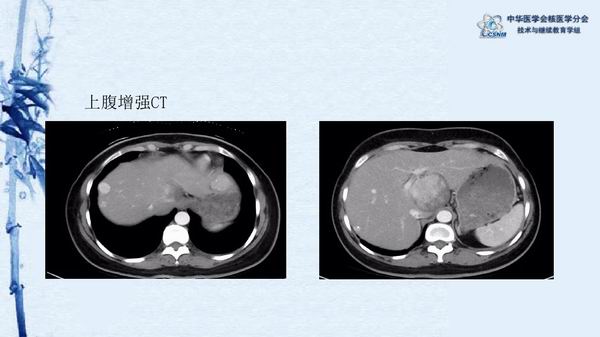

病例45:卵巢结节性甲状腺肿伴乳突状癌-【CSNM继教学组】农天雷 柳州市柳铁中心医院